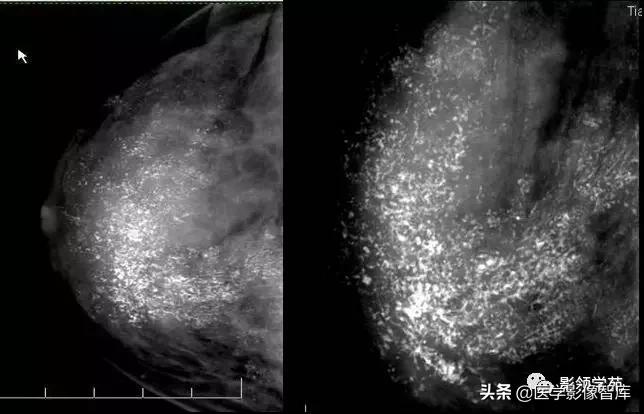

无定形钙化

- BI-RADS2: 双侧且弥漫

- BI-RADS3:多发,双侧,簇状

- BI-RADS4:单侧簇状或者随访患者乳腺对侧新发。